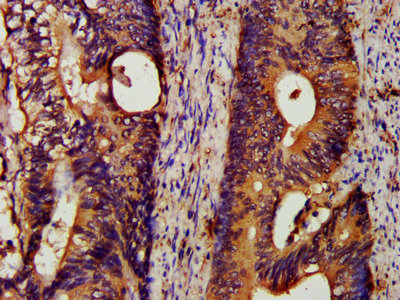

IHC image of CSB-PA05027A0Rb diluted at 1:200 and staining in paraffin-embedded human colon cancer performed on a Leica BondTM system. After dewaxing and hydration, antigen retrieval was mediated by high pressure in a citrate buffer (pH 6.0). Section was blocked with 10% normal goat serum 30min at RT. Then primary antibody (1% BSA) was incubated at 4°C overnight. The primary is detected by a biotinylated secondary antibody and visualized using an HRP conjugated SP system.